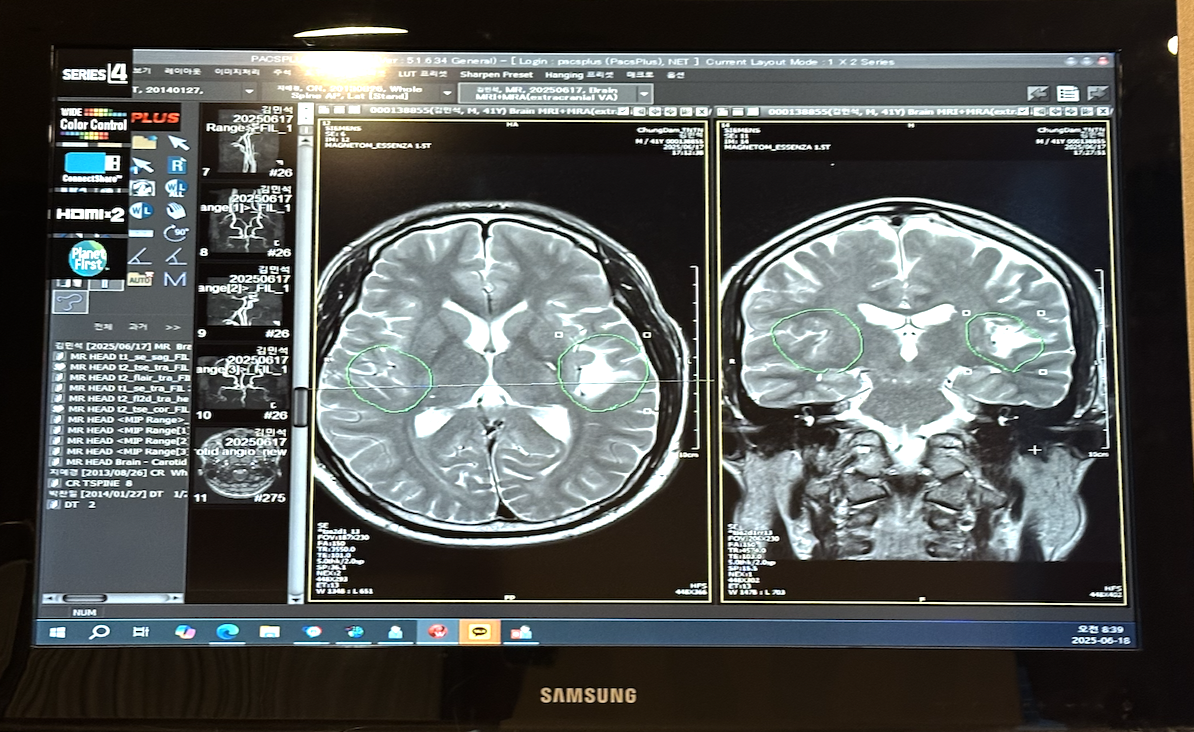

지금까지 여러 번 이직을 경험했고 15개월 간 육아를 위한 공백기간도 있었지만, 이번엔 정말 이상한 이유로 퇴사를 하게 되었다. 바로 뇌 MRI 사진을 찍게 된 것.

스크린샷 2025-07-07 오후 4.11.19.png 뇌 MRI 사진 : 좌측 뇌의 일부분이 소실된 것을 볼 수 있다

그런데 충격적이었던 건 뇌 MRI 사진이었다. 의사 선생님은 유럽 리그에서 한쪽 다리 없이 축구를 하는 손흥민 같다고 했다.

공부를 잘할 수 없는 뇌, 머리 쓰는 일을 할 수 없는 뇌

초등학교 때 뇌졸중의 영향으로 언어적인 부분을 담당하는 좌뇌 영역에 데미지가 있는 상태였다. 사진을 보면.. 정말 없었다. 듣고 정리하는 능력, 기억하는 능력, 말하는 능력 부분을 처리하는 영역에 데미지가 있었다. 난 공부를 해서 이만큼 이루었고(게다가 수능 언어영역은 1등급이었다.) 지금은 컨설팅을 하고 있는데 어찌 된 일일까.

정말 미친 노오력으로, 그리고 선천적인 예민함과 똑똑함으로. 그리고 손상된 곳 주변 뇌와 우뇌의 캐파까지 끌어다 써서 겨우겨우 지금까지 왔다고 한다. 원래는 불가능하단다. 양쪽이 다 멀쩡했으면 한강 작가가 되었을 거란다. 의사 선생님이 엄지손가락을 드셨다. 그동안 듣고 이해하고 정리하고 말하는 부분에서 순발력이 부족하다는 생각을 많이 했었고, 그런 부분을 커버하려 발버둥 쳤지만 쉽지 않았는데 이제 이해가 되었다.